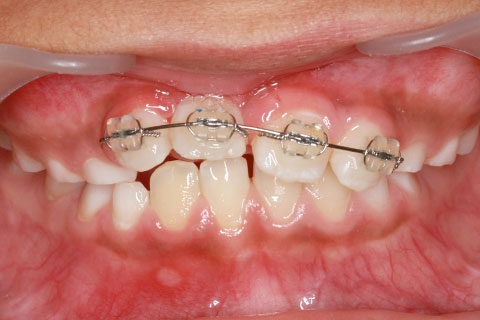

3ヶ月後

マルチブラケットを用いた矯正治療